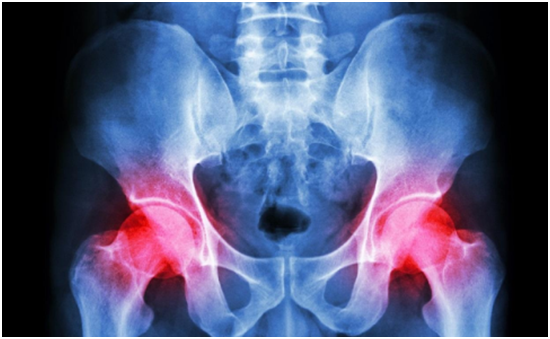

(1)要早期发现骨肿瘤,可以通过抽血以及相关辅助检查来明确诊断。抽血主要是进行一些肿瘤标志物的抽血检查。(2)如果是较大的肿物,常规进行X线便可观察到肿物的存在。但如果是一些较小的肿物,还需要通过CT或磁共振来明确诊断,必要时甚至还可以进行PET-CT检查来明确全身是否有多发肿瘤。(3)在发现肿瘤后,可以在X线、CT、B超介导下取肿瘤组织进行活检,明确其良恶性,但有时如果肿物较小,很可能会取到正常的组织,所以必要时需要进行手术切除肿物来进行病理检查。(1)疼痛,为骨肿瘤早期出现的主要症状,病初较轻,呈间歇性,随病情的进展,疼痛可逐渐加重,发展为持续性。多数患者在夜间疼痛加剧以致影响睡眠。其疼痛可向远处放射。(2)肿胀或肿块,位于骨膜下或表浅的肿瘤出现较早,可触及骨膨胀变形。如肿瘤穿破到骨外,可产生固定的软组织肿块,表面光滑或者凹凸不平。(3)功能障碍,骨肿瘤后期,因疼痛、肿胀而患部功能将受到障碍,可伴有相应部位肌肉萎缩。(4)压迫症状,向颅腔和鼻腔内生长的肿瘤,可压迫脑和鼻的组织,因而出现颅脑受压和呼吸不畅的症状;盆腔肿瘤可压迫直肠与膀胱,产生排便及排尿困难;脊椎肿瘤可压迫脊髓而产生瘫痪。(5)畸形,因肿瘤影响肢体骨骼的发育及坚固性而合并畸形,以下肢为明显。(6)病理性骨折,肿瘤部位只要有轻微外力就易引起骨折,骨折部位肿胀疼痛剧烈,脊椎病理性骨折常合并截瘫。(7)全身症状,骨肿瘤后期由于肿瘤的消耗、毒素的刺激和痛苦的折磨,可出现一系列全身症状,如失眠、烦躁、食欲不振、精神萎靡、面色苍白,进行性消瘦、贫血、恶病质等。(1)局部肿块:为最早出现的症状,表现为坚实而无压痛,表面光滑,可为单发,也可为多发医`学教育网搜集整理。(2)疼痛:大多数良性骨肿瘤没有疼痛,少数除外(如骨样骨瘤)。(3)生长缓慢:肿瘤增大较慢,可在很长时间内肿瘤无变化,若肿物生长突然加快,要考虑恶变可能。(4)病理性骨折:少见,多发生于髓内病变者(如骨囊肿、骨纤维结构不良等)。(5)X线表现:肿瘤边界清楚、整齐,与正常骨有清晰的界限,常见有一反应性致密带;肿瘤一般不浸润软组织;有些肿瘤局部可呈囊性膨胀性骨质破坏;骨膜反应增生少见。(1)疼痛:关节附近出现固定性、持续性及渐进性的疼痛为恶性骨肿瘤最早出现的症状,夜间痛比较明显,疼痛突然剧烈可能是由于病理性骨折所致。(2)肿块:增大迅速,常伴有局部皮肤发热,浅静脉怒张,肿块边界不清(5)局部压迫症状:明显,常因肿瘤生长迅速压迫周围神经、血管而出现相应压迫症状。(6)实验室检查:血清碱性磷酸酶升高多见于恶性骨肿瘤如骨肉瘤。(7)X线表现:肿瘤破坏区边界毛糙不清;破坏区轮廓完整,骨皮质残缺不全;肿瘤可突破骨皮质及骨膜在软组织内形成肿块;破坏区可见形态数量不一、分布紊乱及轮廓模糊的瘤骨或钙化征象;常见骨膜反应增生。(1)骨软骨瘤:这些肿瘤占所有良性骨肿瘤的40%以上。它们主要存在于儿童和青少年中。骨软骨瘤是一种生长异常,发现于长骨的生长末端。骨软骨瘤可能单独生长,也可能伴有其他类似的肿瘤。(2)破骨细胞瘤:也被称为骨巨细胞瘤。长管状骨约占75-90%、长骨的骨端约占98-99%、膝关节周围约占55%。20-50岁:占80 % 15-20岁:占10%,<15岁:占2%,骨骺闭合后:98%,骨骺闭合前:占2%。(3)骨样骨瘤:多发生于5~20岁的儿童和青少年,男女发病率之比约为2:1。最常见的发病部位在下肢长骨,其次是上肢骨,脊柱、手、足等部位则较少见。(4)内生软骨瘤:它是始于软骨的骨肿瘤。它主要存在于骨骼内层的软骨中。脚和手的短骨受影响最大。青少年比其他年龄组受影响更大,大多20岁以后发病(5)非骨化性纤维瘤:常见于儿童及青少年,属于常见的发育异常,约35%的儿童会发生,5~20岁最多见。40%位于股骨远端,40%位于胫骨近端,10%位于腓骨。(1)骨肉瘤:最常见的原发恶性骨肿瘤,多发于10-20岁阶段青少年,好发部位为股骨远端,胫骨近端和肱骨近端的干骺端。(2)软骨肉瘤:是软骨分化的恶性肿瘤。特点是肿瘤细胞产生软骨,常出现黏液样变、钙化和骨化。好发于成年人和老年人,男多于女。常见发病部位是骨盆、股骨近端、肱骨近端和肋骨。(3)尤文肉瘤:多发于儿童,常见于长骨骨干、骨盆和肩胛骨。(4)浆细胞性骨髓瘤:起源于骨髓造血组织,能最终浸润到全身各个器官。多发生于40岁以上男性,好发部位为含有造血骨髓的骨骼,以此为脊椎、骨盆、肋骨、颅骨和胸骨等。(5)恶性纤维组织细胞瘤:是源于纤维组织的一种的原发性骨恶性肿瘤,好发于四肢长骨干骺端,以股骨多见。恶性肿瘤:采用化疗、手术为主,包括放疗、免疫治疗、内分泌治疗、冷冻治疗、温热治疗及中医药治疗等手段的综合治疗。对于恶性骨肿瘤来说,其基本的治疗原则可以概括为:“三保”,即:保命、保肢、保功能。以前需要截肢的很多四肢恶性骨肿瘤,随着近年来诊断以及治疗技术的提高,目前大部分都可采取刮除、切除术、或瘤段切除 + 重建术等先进方法保全肢体。而且目前有很好的放疗、化疗、生物治疗、中医治疗等综合治疗措施。使很多肿瘤治疗效果较以前大大提高。即便是很多来源于其他器官系统转移过来的骨肿瘤,近年来,微创技术在骨肿瘤治疗方面也有了巨大发展。